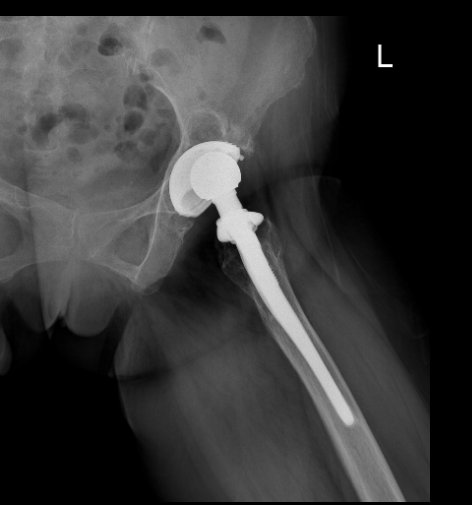

60 余岁的杨阿姨因左侧髋部疼痛伴活动受限 6 月余,加重 1 天入院就诊。

追溯病史可知,患者 20 余年前因股骨头坏死接受左侧全髋关节置换术,术后初期恢复良好,但随着假体使用年限增长,逐渐出现关节磨损与脱位,近半年症状显著加重。

影像学检查提示,其所用假体为 2001 年的产品,因技术迭代已停止应用,且存在髋臼严重缺损(术中可见 "陨石坑" 样骨缺损)及臀中肌完全缺失等复杂情况。